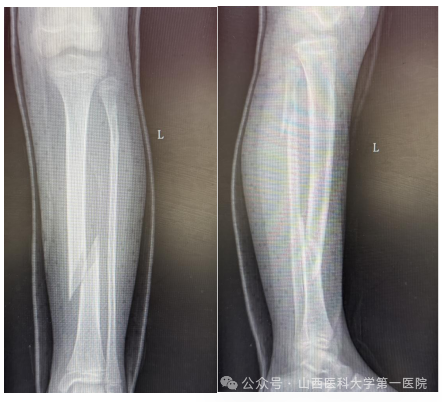

9岁女孩王某某在家中不慎滑倒后导致左小腿胫腓骨螺旋骨折,家长焦急万分,为了获得更好的治疗来到51风流

骨科门诊,杨自权主任详细评估患者病情后收入病房继续治疗。

儿童胫腓骨骨折多因外伤导致,因儿童骨膜厚、愈合快、塑性能力强,因此微创治疗可减少手术创伤、降低并发症。但王某某为左侧胫腓骨螺旋骨折,骨折断端移位大、稳定性差,若行微创手术复位无疑增加了手术难度。杨自权主任团队分析病情后,考虑患者仅为9岁女孩,最后计划使用闭合复位儿童弹性髓内钉(ESIN)内固定术,微创手术瘢痕小,在保留美观的同时尽可能减少对儿童骨骼生长发育的影响。